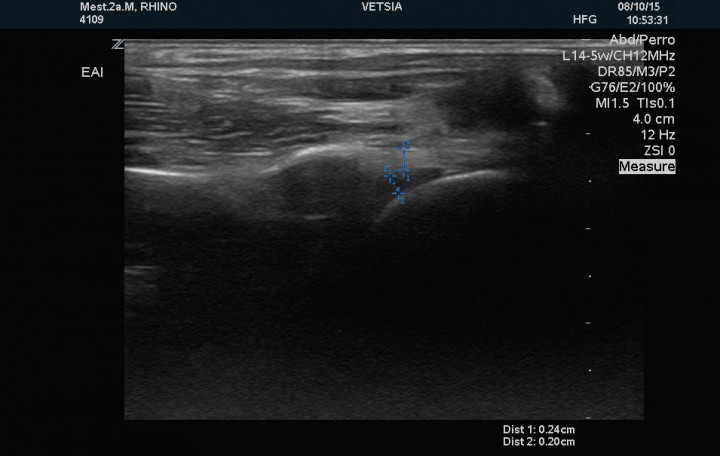

Se realizó examen ecográfico de ambas articulaciones escápulo-humerales con sonda lineal de 12 MHz; los hallazgos ecográficos observados en la articulación izquierda mostraron un tendón del músculo infraespinoso de estructura normal y 2,8 mm de grosor en corte transversal, el tendón del músculo supraespinoso presenta un grosor de 1,7 mm en su porción tendinosa, 4,2 mm en la transición fribrocartilaginosa y de 7,2 mm en la porción fibrocartilaginosa próxima al tubérculo mayor del húmero (zona de máximo grosor), evidenciándose en esta región, próxima a la superficie perióstica, una estructura ecogénica que producía una sombra acústica distal de 3,7mm de diámetro compatible con un foco de mineralización intratendinosa (Fig. 2). El tendón del músculo bíceps braquial presenta su inserción normal en la tuberosidad supraglenoidea con un grosor de 2,7 mm, mostrando su cápsula sinovial un engrosamiento en su porción más proximal (Fig. 3). La cabeza humeral y el cartílago articular se evidencian de contorno liso y grosor normal. La articulación escapulo-humeral derecha no presentaba ningúna alteracion (Fig. 4). La imagen ecográfica es compatible con tendinopatía del tendón del músculo supraespinoso, con mineralización en fibrocartílago de 3,7 mm y signos leves de sinovitis del bicipital.

Corte sagital del tendón del músculo supraespinoso izquierdo en el que se muestra la mineralización (entre los cursores) como una superficie ecogénica irregular con sombra acústica posterior.

Al finalizar la segunda fase del tratamiento de rehabilitación se repitió la exploración ecográfica. Dicho examen evidenció un tendón del músculo infraespinoso de 2,3 mm de grosor, el tendón del músculo supraespinoso presentaba un grosor de 1,9 mm en su porción tendinosa, 4,0 mm en la transición fibrocartilaginosa y de 6,9 mm en el fibrocartílago, con un foco de mineralización de 1,7 mm de diámetro (Fig. 5). El tendón del músculo bíceps presentaba un grosor de 2,7 mm y la cápsula sinovial se observó de grosor normal, sin evidencia de signos de tenosinovitis (Fig. 6).

Corte sagital del tendón del músculo supraespinoso izquierdo posterior al tratamiento, en el que se observa disminución de la mineralización del tendón (medida número 4).